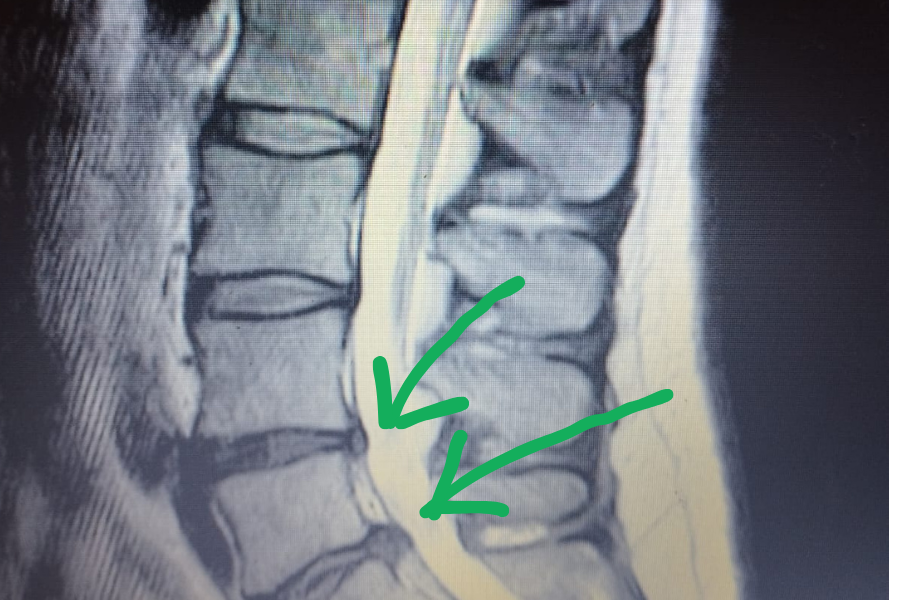

Fıtık Nedir? Ne İyi Gelir? Fıtığın Tedavisi Nasıl yapılır?

Omurgamızda çok önemli bir role sahip olan vertebralar  arasındaki kıkırdak (disk); şok absorbe etmek  ve omurganın her yöne doğru hareket etmesine olanak sağlar.  Eğer bu diskler […]